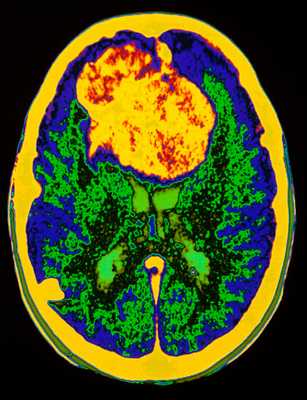

МРТ головного мозга. Сагиттальная и аксиальная Т1-взвешенные МРТ, аксиальная Т2-взвешенная МРТ и аксиальные КТ и Т1-взвешенная МРТ с контрастированием. Гигантоклеточная астроцитома с кальцификацией - внутрижелудочковая опухоль.